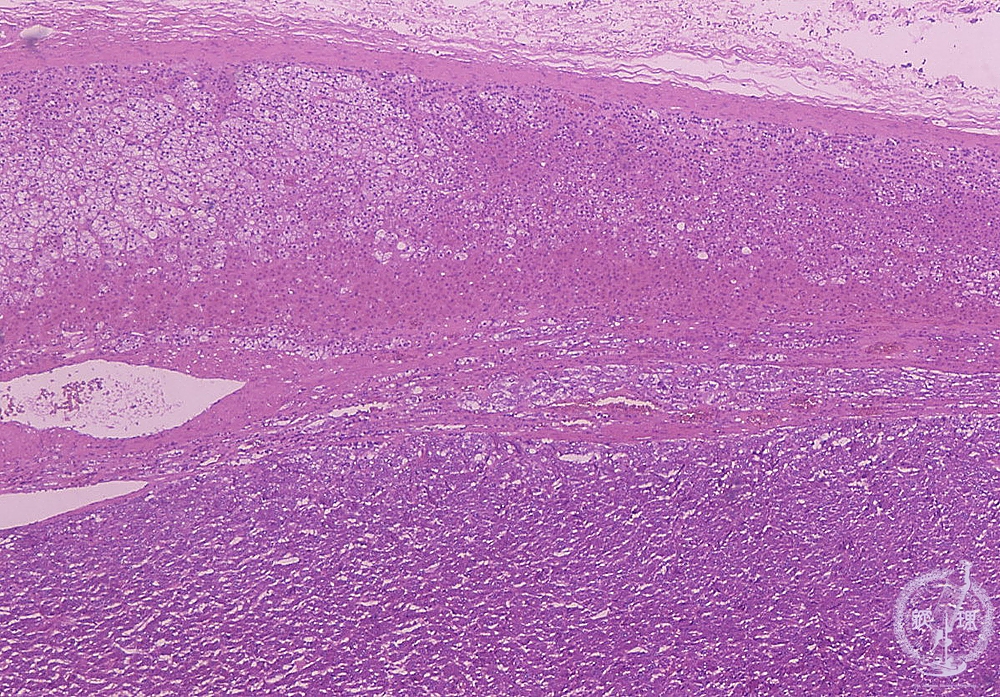

- ★(14)Pheochromocytoma

Microscopic findings (HE stain, low power view). Proliferation of the tumor cells (arrows) in the medulla of the adrenal gland.